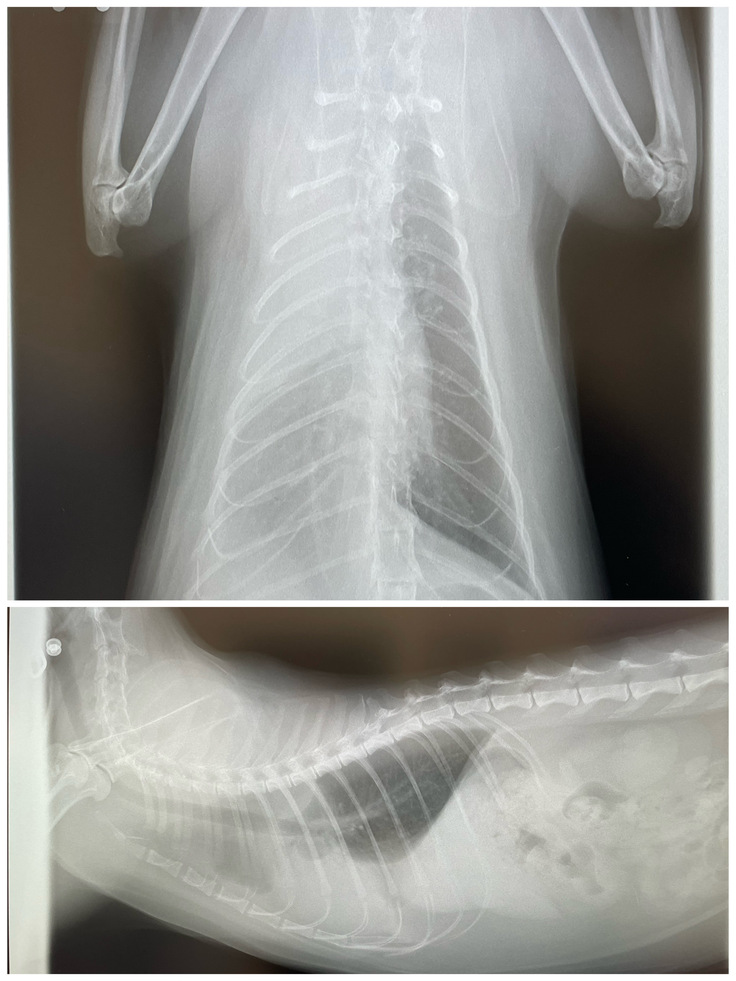

レントゲン検査では、心臓や肺が映らないほど胸水が溜まっていることが判明し、じじまるは、そのまま即入院となりました。

(正面図:右肺が全くうつらない)

(側面図:心臓も肺も全くうつらない)

(ドレーン手術後のレントゲン。胸水は膿水ということがわかり、生理食塩水で洗浄し薄めながら徐々に取り出すことに)

1週間程、ドレーンにて膿胸の洗浄排出を繰り返しようやく心臓と肺の影が見えてきました。

(ドレーンが肺上部に入っているのがわかる)

(正面図:右肺がやはりうっすらぼやけている)

(側面図:心臓は見え出したがまだぼやけている)